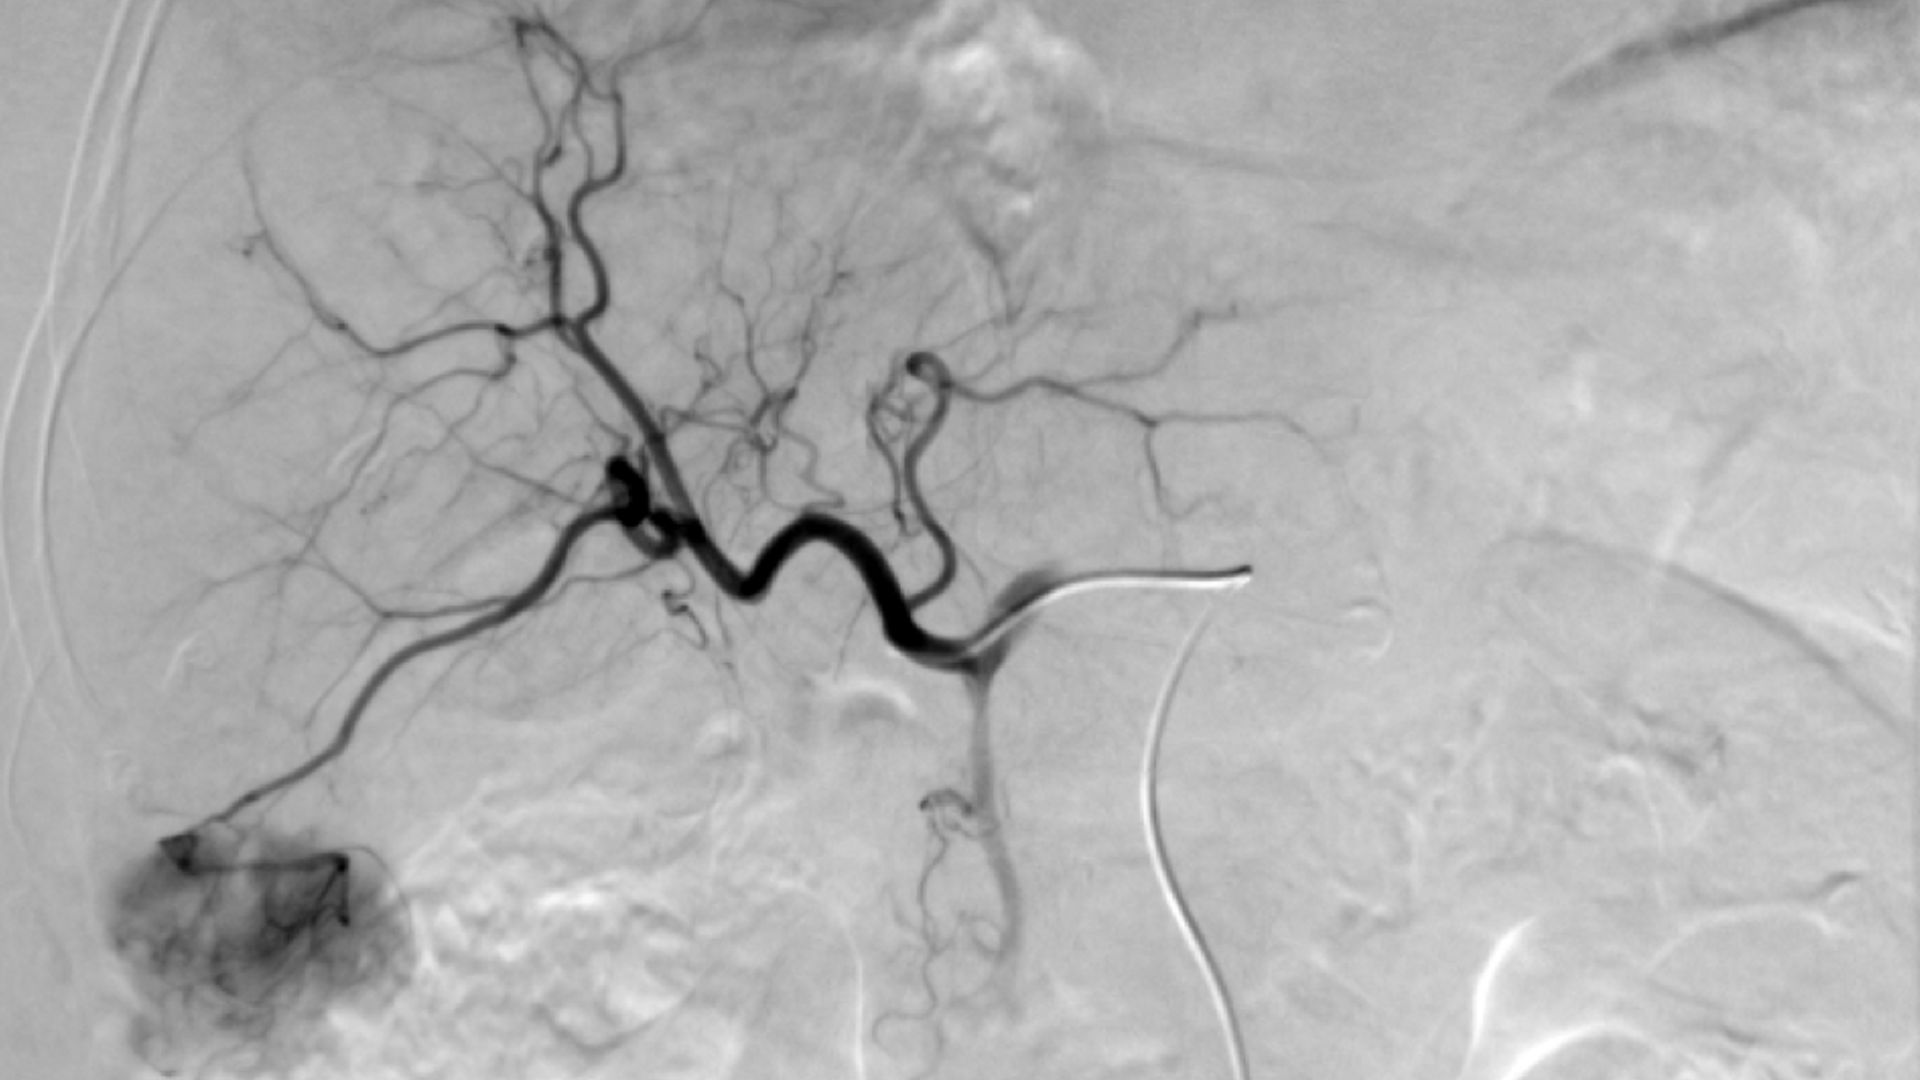

La prova consta d’una punxada en un vas sanguini, generalment a l’engonal. S’aplica anestèsia local i s’introdueix un tub molt prim (catèter), a través del qual s’injecta un líquid (contrast) que permet veure els vasos sanguinis. Mitjançant la circulació s’arriba directament al fetge, on s’administra la quimioteràpia en el tumor hepàtic. Es tapen alguns vasos sanguinis del fetge perquè la medicació hi romangui més temps i aconsegueixi un efecte més gran.